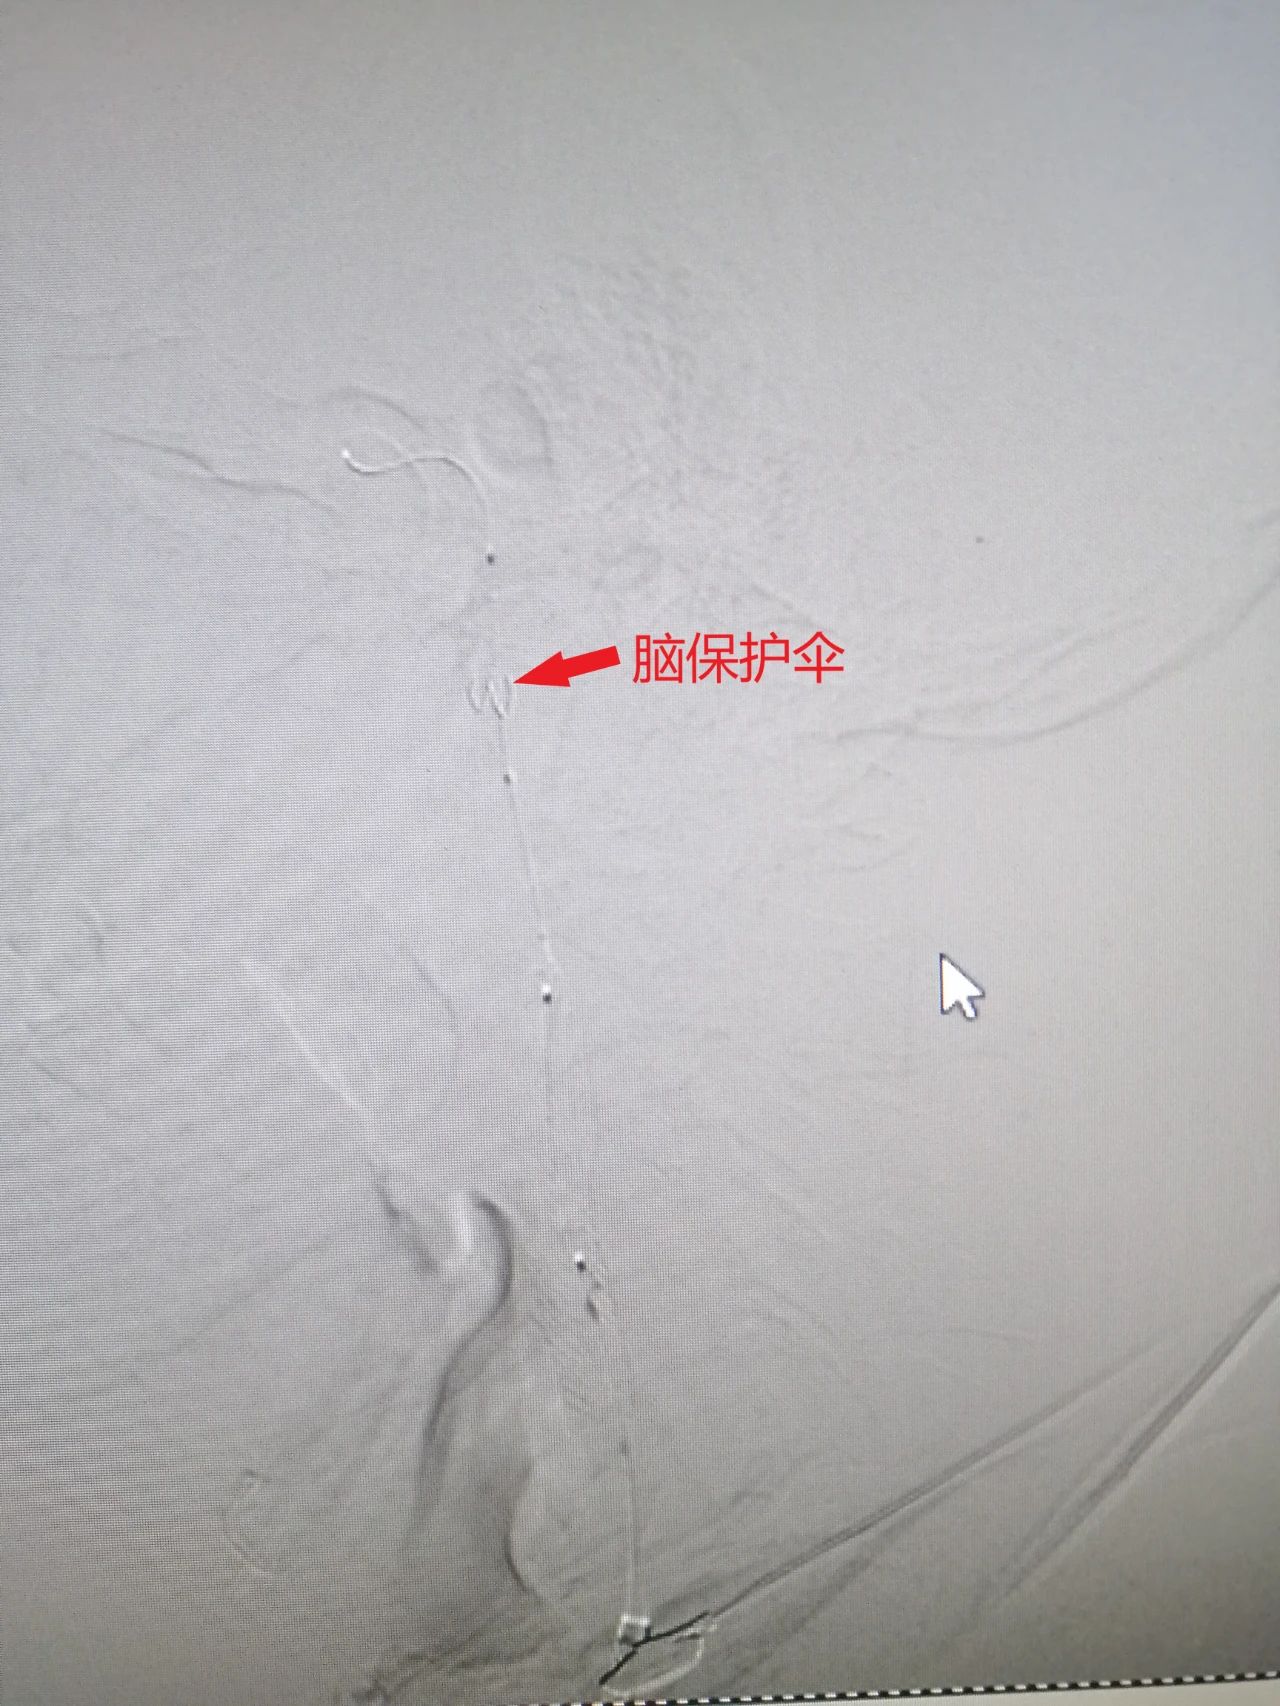

支架置入

脑保护伞保护下颈内动脉支架置入术,是将脑保护装置送到狭窄部远端,释放形成一只像雨伞一样的滤器,伞上的小孔允许血液通过,但脱落的颈动脉狭窄斑块、血栓则被挡住。

颈动脉狭窄操作完成后保护伞可以像雨伞一样收拢,将收于其中的斑块、血栓带出,极大地减少了颈动脉狭窄支架置入术的并发症。